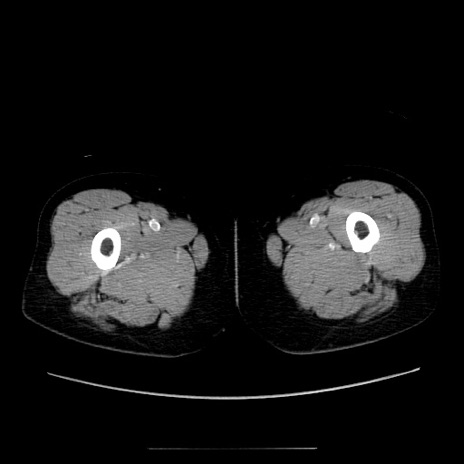

症例5(横断像)

【症例】70歳代女性

【主訴】お腹が張る

【現病歴】1週間くらい前から腹部膨満の自覚あり。昨日夜から増悪したため、本日救急外来受診。

【身体所見】意識清明、BT 36.5℃、BP 165/106mmHg、HR 80bpm、SpO2 98%、腹部:膨満、軟、自発痛・圧痛なし、触診にて不快感あり、腸蠕動音:減弱

【データ】WBC 12600、CRP 1.04